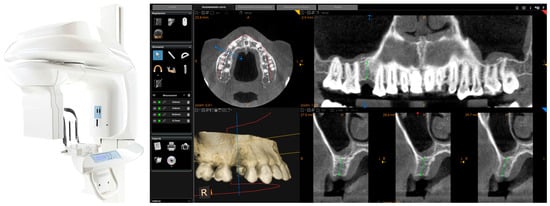

Each of the patients selected for inclusion in the present prospective study was subjected to intraoral scan of the arches, with a powerful structured light scanner (CS 3600®, Carestream Dental, Atlanta, GA, USA) (Figure 1).

Intraoral scan CS 3600® (Carestream Dental, Atlanta, GA, USA). The second right premolar (#15) is missing and an implant is going to be planned. (A) Occlusal view. (B) Lateral view.

This scan was performed in orthodontic mode, and consisted of a scan of the master model (site of the edentulism), of the antagonist, and of the capture of the bite (occlusion). During the scan, the operator took care to capture every morphological detail of the teeth adjacent to the implant, i.e., those selected to support the future surgical guide. At the same time, special attention was paid to the scanning of soft tissues in the area of edentulism. The files thus acquired were saved in .STL format in a special folder. In the same session, the patient was then subjected to 3D radiological examination with cone beam computed tomography (CBCT), using a powerful scanner with adjustable field-of-view (CS 9300®, Carestream Dental, Atlanta, GA, USA) (Figure 2).

Figure 2.

CBCT with CS 9300® (Carestream Dental, Atlanta, GA, USA). The first visualization of the CBCT reveals sufficient bone volume (height and width) to plan the position of a dental implant.

The planning of the case involved the use of two different sets of software: A prosthetic CAD (computer-assisted-design) (EXOCAD®, Darmstad, Germany) for the virtual wax-up and a surgical CAD (SMOP®, Swissmeda, Baar, Switzerland) for 3D planning of implant placement and the design of the surgical template (Figure 3).

Figure 3.

The implant is planned with the aid of a guided surgery software (SMOP®, Swissmeda, Baar, Switzerland). A 3.75 mm × 10 mm implant (BT Safe Bone Level®, BTK, Dueville, Italy) is therefore planned.